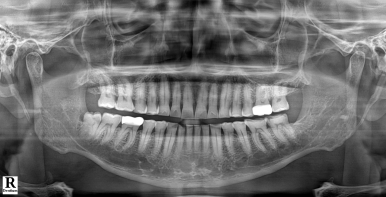

🦷 이갈이를 방치하면 생기는 문제

이갈이는 수면 중 무의식적으로

치아를 강하게 맞물리는 행동입니다.

문제는 그 힘이

👉 음식 씹는 힘보다 훨씬 강하다는 점입니다.

이로 인해 다음과 같은 문제가 생길 수 있습니다.

✔ 치아 마모 → 시림, 민감증 증가

✔ 치아 파절 → 금이 가거나 깨짐

✔ 보철물 손상 → 크라운, 임플란트 수명 단축

✔ 턱관절 장애 → 통증, 소리, 입 벌릴 때 불편함